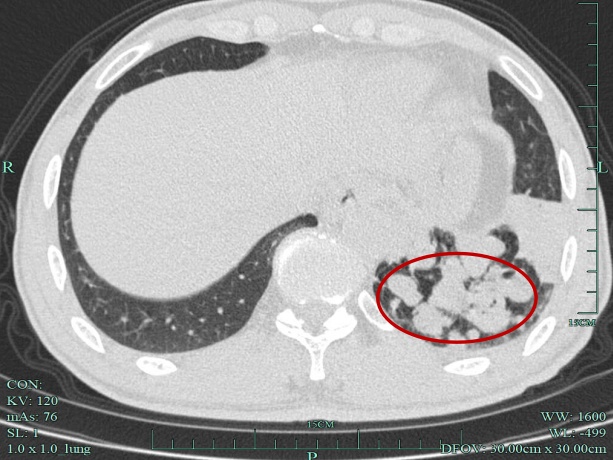

接诊的汝触会主任仔细问诊及查体后,发现张师傅年轻时有过肺结核感染史。结合这一重要信息,汝医生为其安排了胸部CT检查。很快,胸部CT影像提示多发囊状支气管扩张,更糟糕的是,这些扩张的支气管里已经被痰栓堵得严严实实。

患者胸部CT可见支气管内痰液堵塞,多发囊状支气管扩张